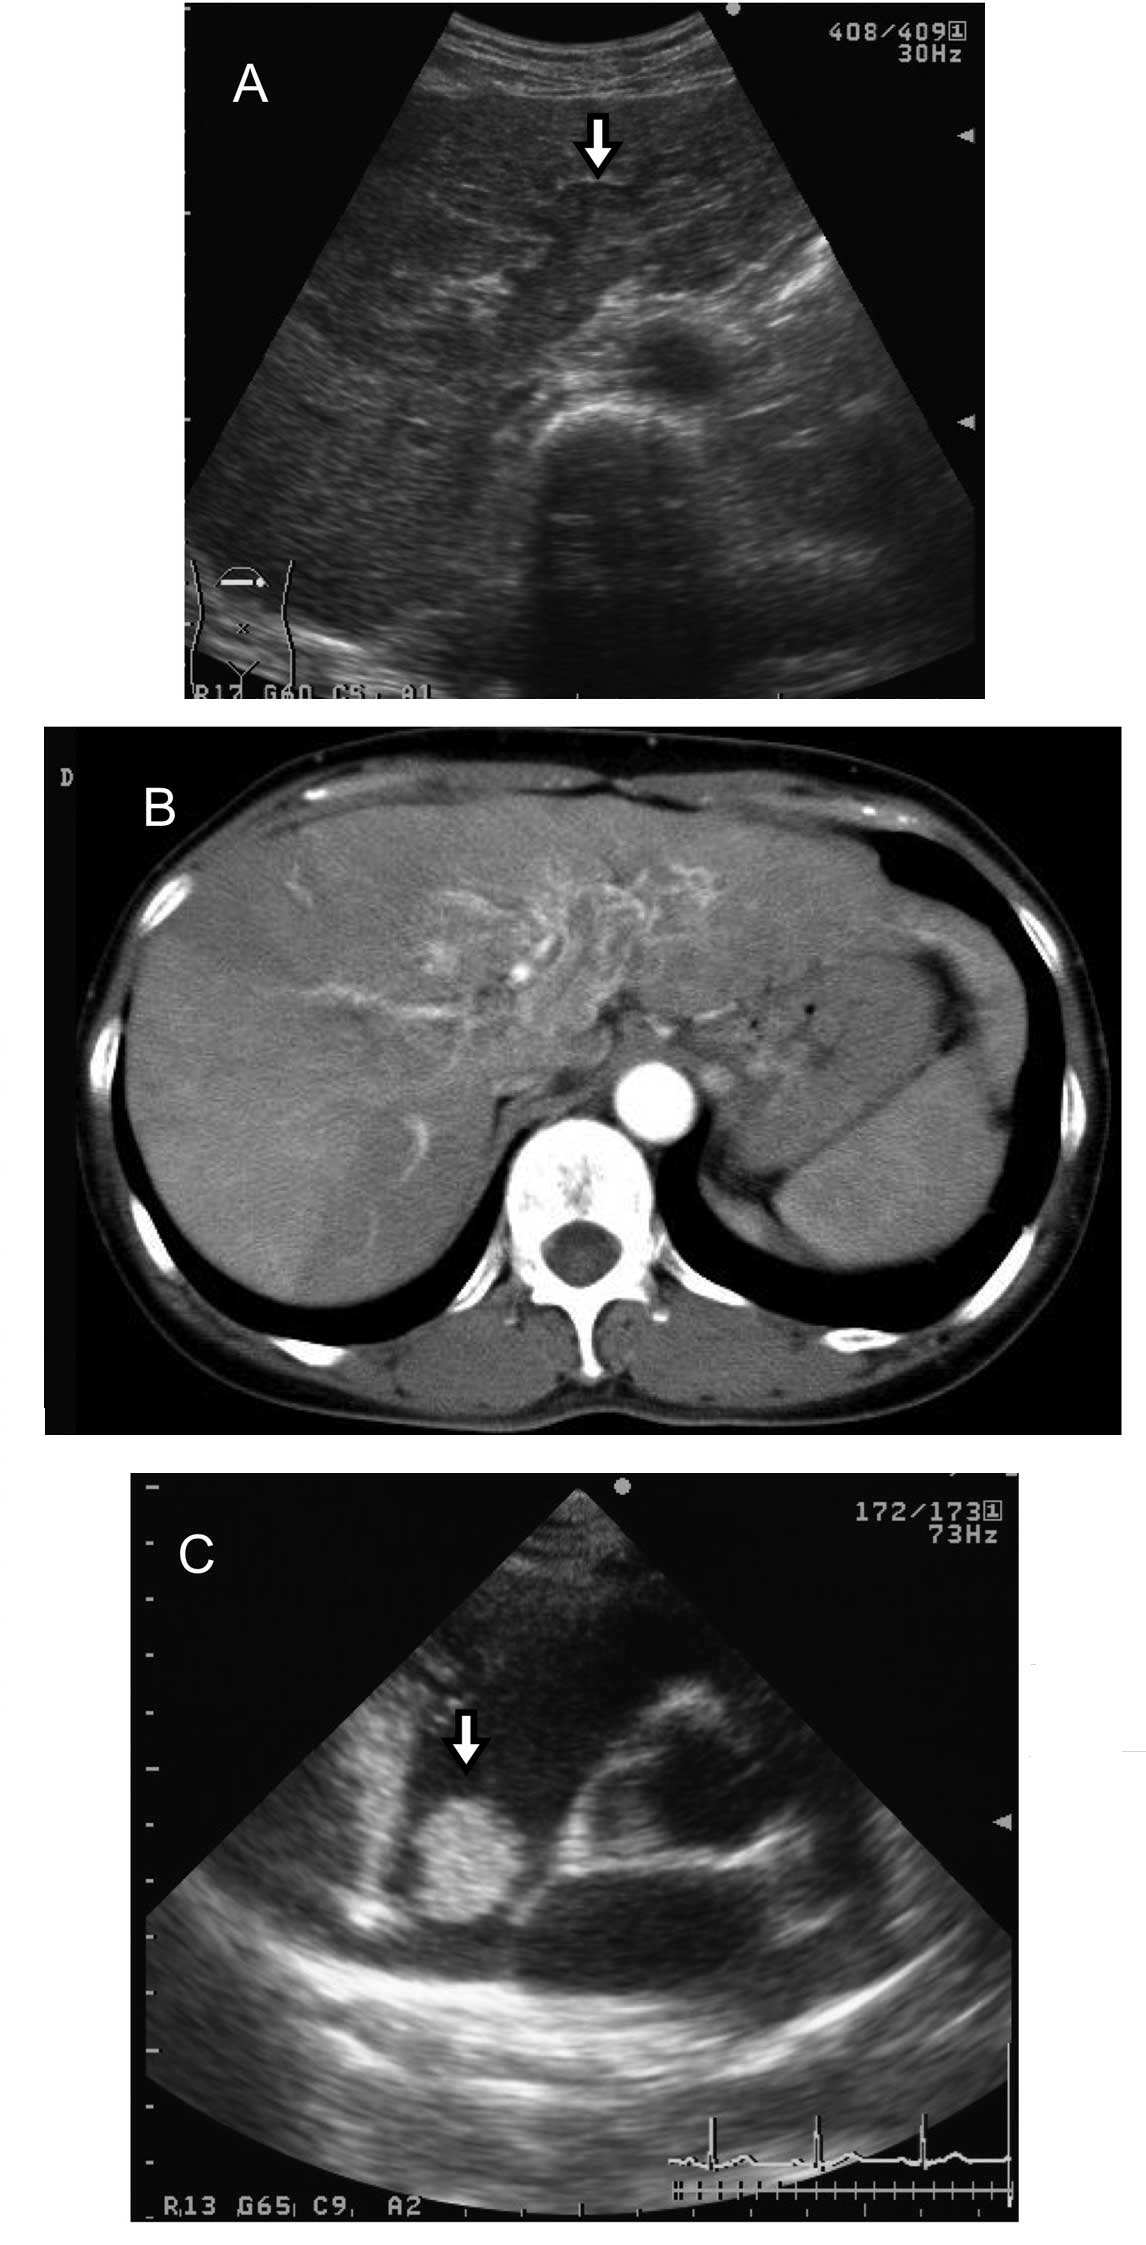

Abdominal sonography and computed tomography (CT) imaging revealed a large mass reaching from the right to the left lobe and a tumor thrombus in the main portal vein (Fig. 1A and B). Angiography revealed a hypervascular tumor in the right lobe exhibiting the thread and streak sign. No metastases were identified in the right atrium (RA) or inferior vena cava (IVC) prior to starting intraarterial chemotherapy with cisplatin, 5-fluouracil, adriamycin and mitomycin.

An enhanced CT in July, 2004, showed that the HCC had progressed and that multiple lung metastases had developed with moderate ascites. Magnetic resonance imaging (MRI) and echocardiography revealed a round, movable tumor with a diameter of 2 cm in the RA (Fig. 1C), but no tumor thrombus in the IVC. The atrial tumor was not continuous with the intrahepatic HCC. Anticoagulation therapy with warfarin was administered, however the patient succumbed to hepatic failure five months later (Fig. 2).